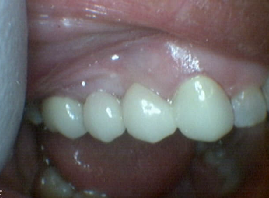

Post-op Bridge – Pre-op Bridge